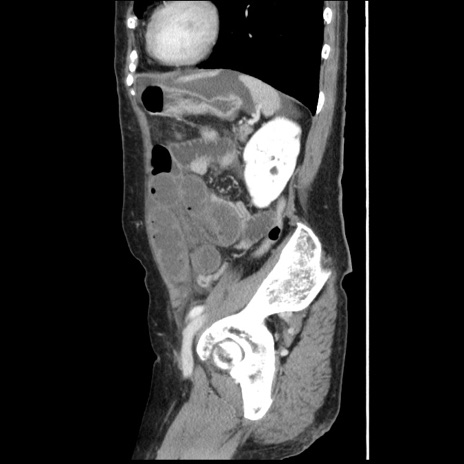

症例1(矢状断像)

【症例】80歳代女性

【主訴】腹痛

【現病歴】8時間前から腹痛あり来院。

【既往歴】糖尿病、脂質異常症、子宮体癌にて子宮全摘術

【身体所見】意識清明・会話良好だが腹痛で苦悶様、全腹部にわたって反跳痛と圧痛あり

【データ】WBC 13600、CRP 0.14、LDH 224、CK 90